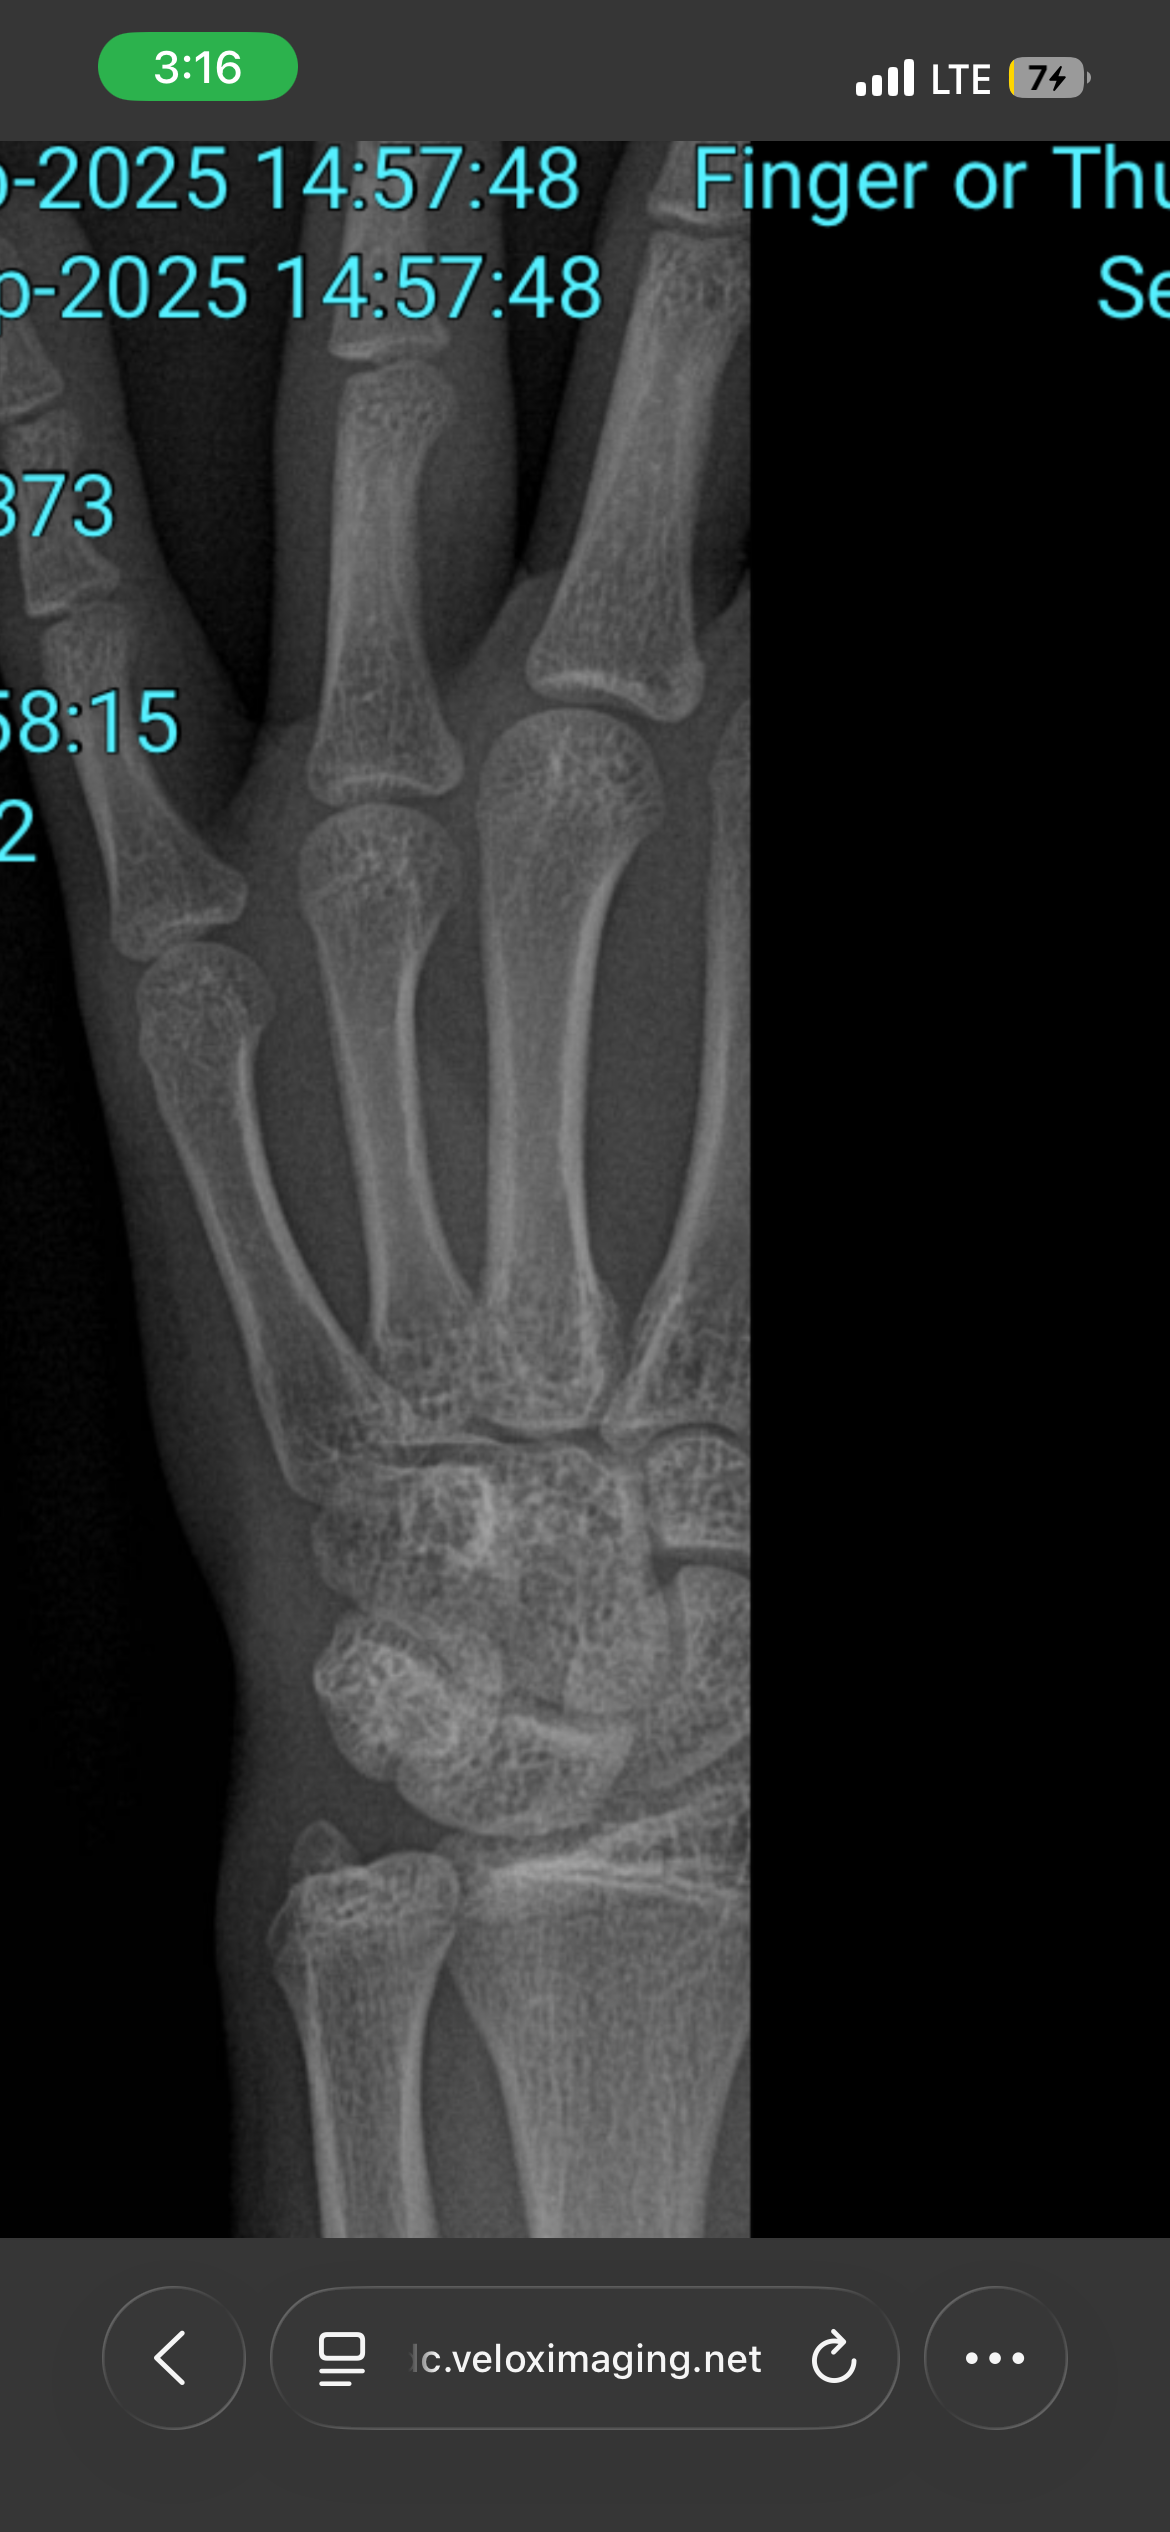

Bassicly im 14 and 10 months at the moment and 5,4, my height has slowed down for a while but im on 12.5mg aromasin eod to keep plates open and mk-677 until i can i get my hands on some gh, ive been on these two for a while like since june. Idk if im cooked tho now with my growth plates i hurt my finger so i got a scan done and they look like they gonna close soon it might be over. Idc abt anything i just want to reach 5,6-5,7 so i wont be an actual subhuman in this society.

can u see the image to see if my plates are open

From my research your plates are barely open this is so brutal You're going to have to blast roids it seems like you have months left I'm not the right guy to ask for roid advice because I'm 5'11 and I only do softmax because I've never been this desperate I'm sorry and I hope you overcome the odds ❤️

Use the stanford bone age calculator thing to see what your bone age actually is

do ur bloodwork see if u have igf and gh deficiency and then figure out what dose works for you but most likely its gonna do fuck all for your height bro your growth plates are cooked. just fraud with height boosters